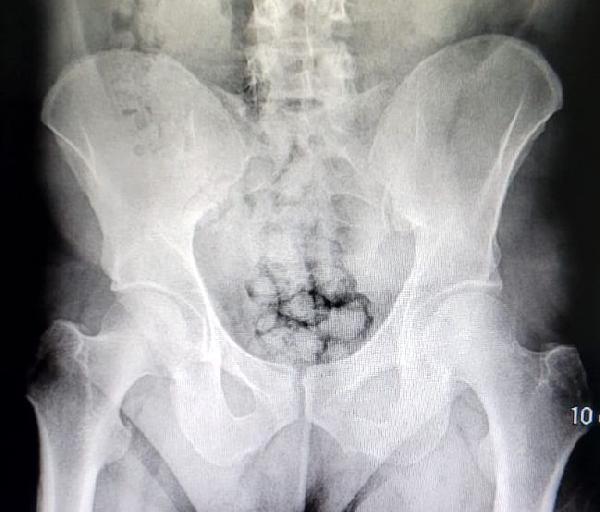

Kayseri’de polis ekiplerince düzenlenen uyuşturucu operasyonunda, midesinde yaklaşık 60 kapsül uyuşturucu taşıyan 2 şüpheli yakalandı. Uyuşturucular röntgen çekimi ile görüldü.

Röntgen çekimi sonrası şüphelilerin midesinde yaklaşık 60 kapsül içinde toplam 500 gram metamfetamin olduğu tespit edildi.